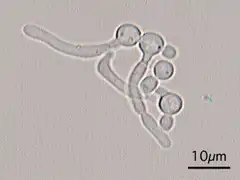

- Germ tubes of Candida albicans